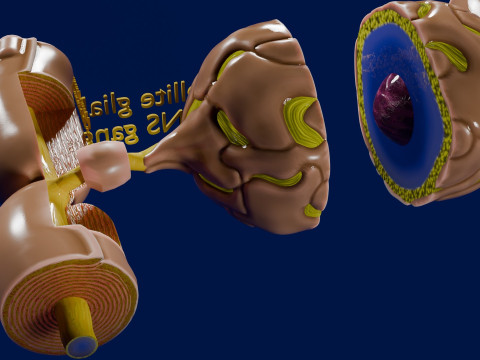

A blend model of brain along with its covering layers (meninges), skull bone and scalp labelled in detail and anatomically precise. The parts depicted are white, gray, pia, arachnoid, dura, bone, skin, fat, aponeurosis, periosteum, falx cerebri and more.

The material is high resolution image textures and normal maps based on non overlapping UVs. The texture and normal maps are packed with the blend file itself.